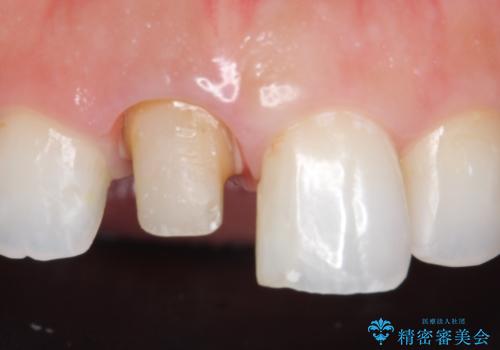

- 右上1の前歯の見た目が気になるので被せ物をやり替えたいといらっしゃった方の症例です。

再根管治療終了後、オールセラミッククラウン(スペシャル)によって隣在歯に合わせた補綴を行いました。